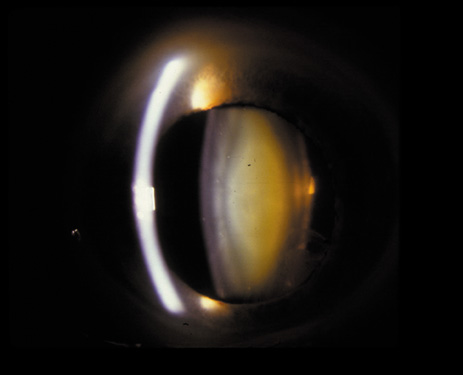

Nuclear cataracts tend to progress slowly. The refractive index of the lens changes as the nucleus progressively hardens, which usually results in increasing myopia.20,21 In some patients this is accompanied by optical distortion, especially of distant images, while near vision remains unaffected. A nuclear cataract is best seen with the narrow-beam direct illumination employed by the slit-lamp, which reveals the color and generalized haze or opalescence of the nucleus. In the early stages, the two halves (cotyledons) of the embryonic nucleus remain visible (Fig. 3). Later the entire nucleus appears as a homogeneous mass in contrast to the cortex (Fig. 4). Retroillumination may show the “oil droplet” effect (Fig. 5). Sometimes one may notice crystals in the lens nucleus (known as a Christmas tree cataract; Fig. 6A and B).

Fig. 3. Early nuclear cataract. Note the “cotyledons” in the nucleus.

Fig. 4. Advanced nuclear cataract. Note the homogeneous nuclear opacity.

Fig. 5. “Oil droplet” appearance of a pure nuclear cataract seen on retroillumination examination.